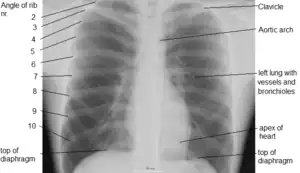

![]() Surface projections of the organs of the trunk, with the thorax or chest region seen stretching down to approximately the end of the oblique lung fissure anteriorly, but more deeply its lower limit rather corresponds to the upper border of the liver. | |